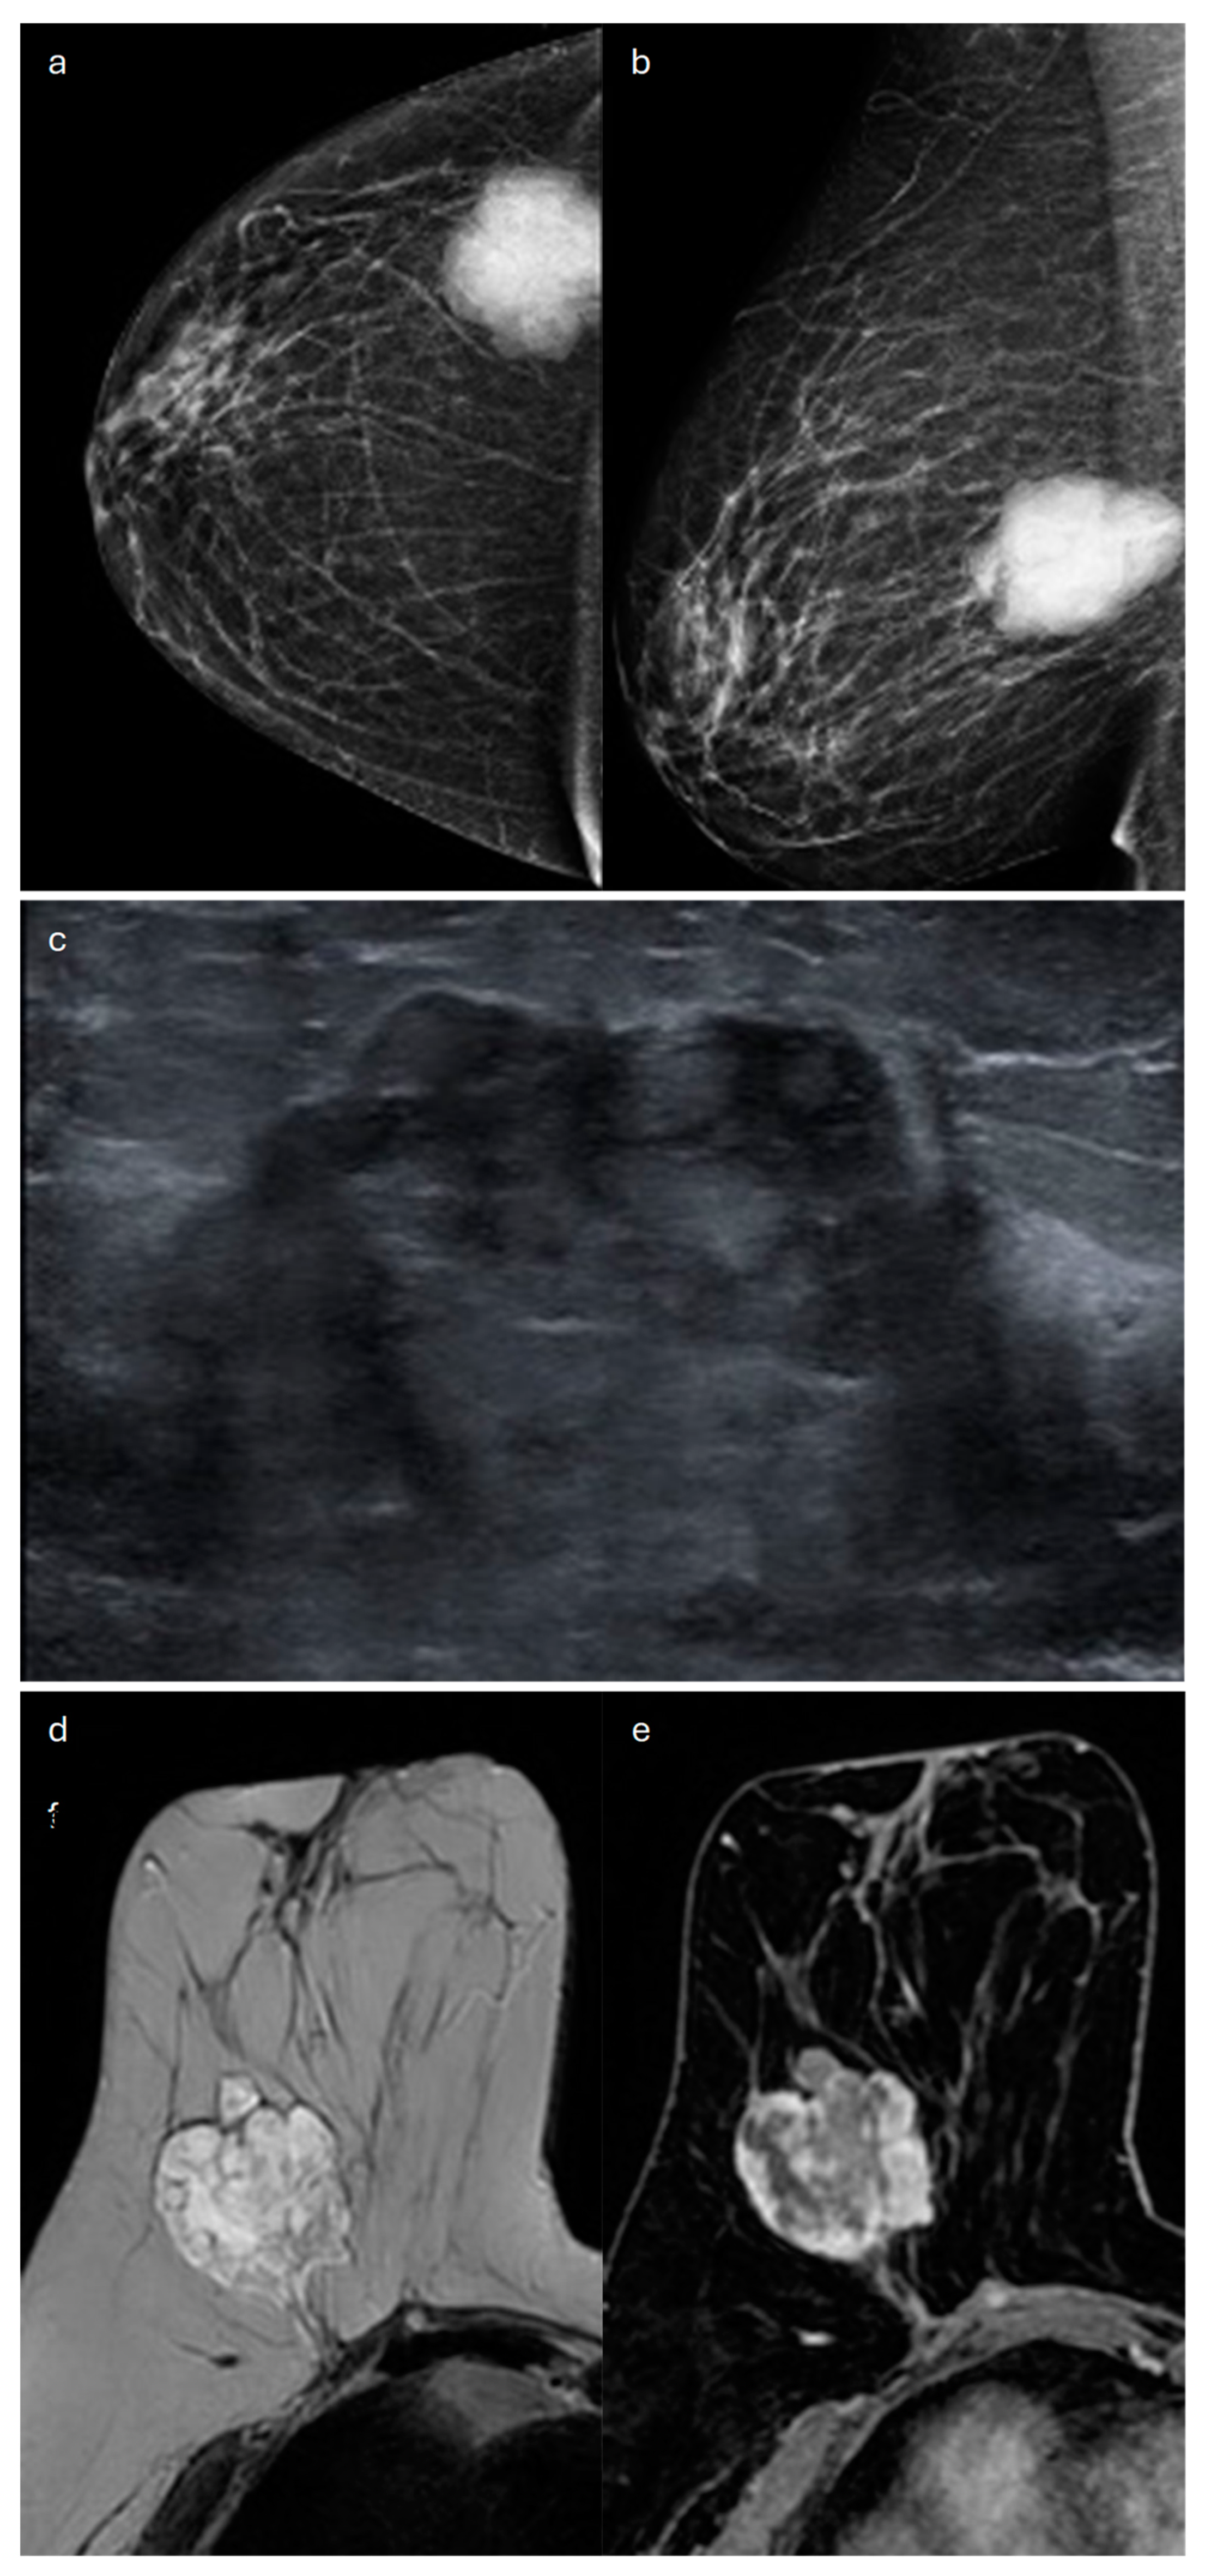

4. Mucinous